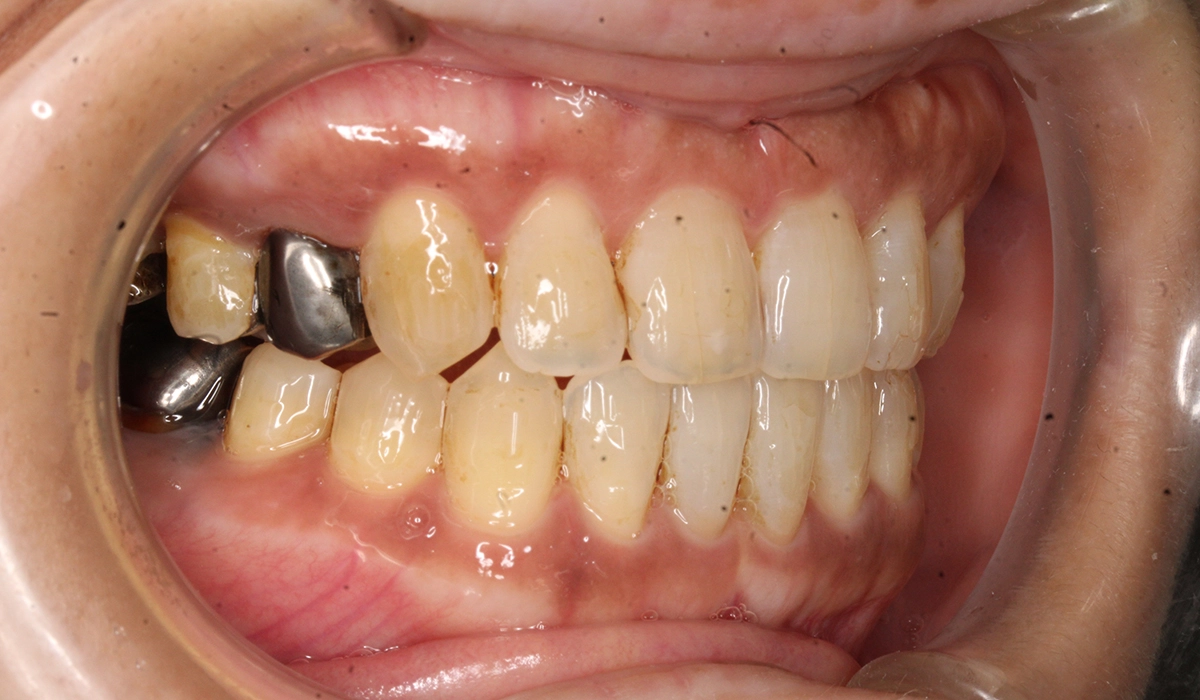

術前:右側